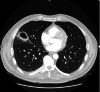

The Streptococcus anginosus group (SAG) consists of three bacteria (Streptococcus intermedius, Streptococcus constellatus, and Streptococcus anginosus) that are known commensals of the upper respiratory, digestive, and reproductive tracts. While a rare occurrence, these bacteria have the capability of causing devastating pyogenic infections and ensuing abscess formations. It is often difficult to distinguish this group as a contaminant or the offending organism (as it is often cultured in respiratory specimens); therefore, it is important to understand the risk factors, clinical presentation, and diagnostic findings that can provide a more accurate picture to identify the organism. Published literature pertaining to the SAG group has rarely documented any invasive surgical intervention that was undertaken for treatment. We describe a case of a 59-year-old male who presented for persistent chest pain and profuse productive cough weeks after he was diagnosed with a left lower extremity deep vein thrombosis and right-sided pulmonary embolism. The patient was found to have a rapidly evolving Streptococcus constellatus right middle lobe lung abscess complicated by a right hemithorax empyema. Management included an exploration of the right chest, decortication, parietal pleurectomy, and partial excision of the right middle lobe. Subsequently, the patient completed four weeks of antibiotics with ertapenem.